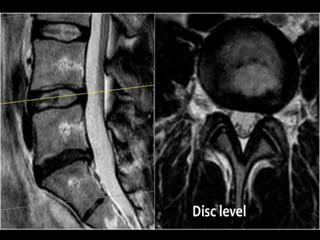

INVESTIGATIONS

MRI

• Clearly superior in the detection of disc

degeneration.

• Allow evaluation of complete spinal group

• Shows:

• Intervertebral disc protrusion.

• Compression of nerve root